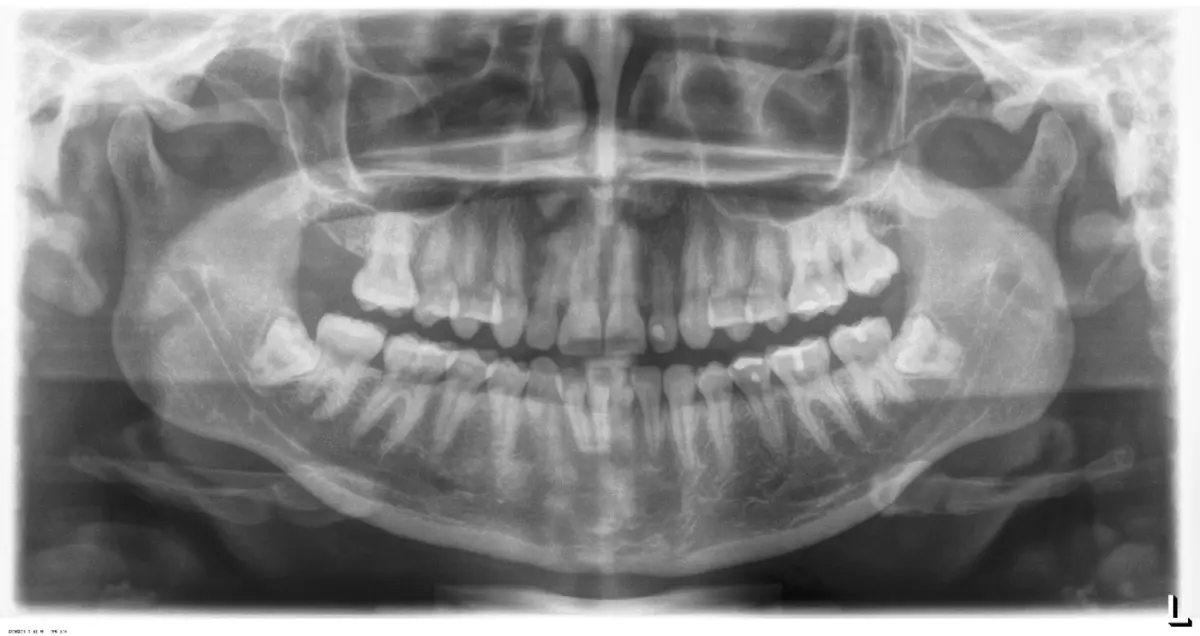

Es imprescindible conocer la ubicación de la tercera molar. Se puede emplear, adicionalmente a la evaluación clínica, herramientas radiográficas (panorámica y periapical) y tomográficas (Cone beam) para determinar la posición, grado de retención y proximidad a estructuras vecinas de riesgo como el nervio dentario inferior y así evitar lesiones (Figura 1).